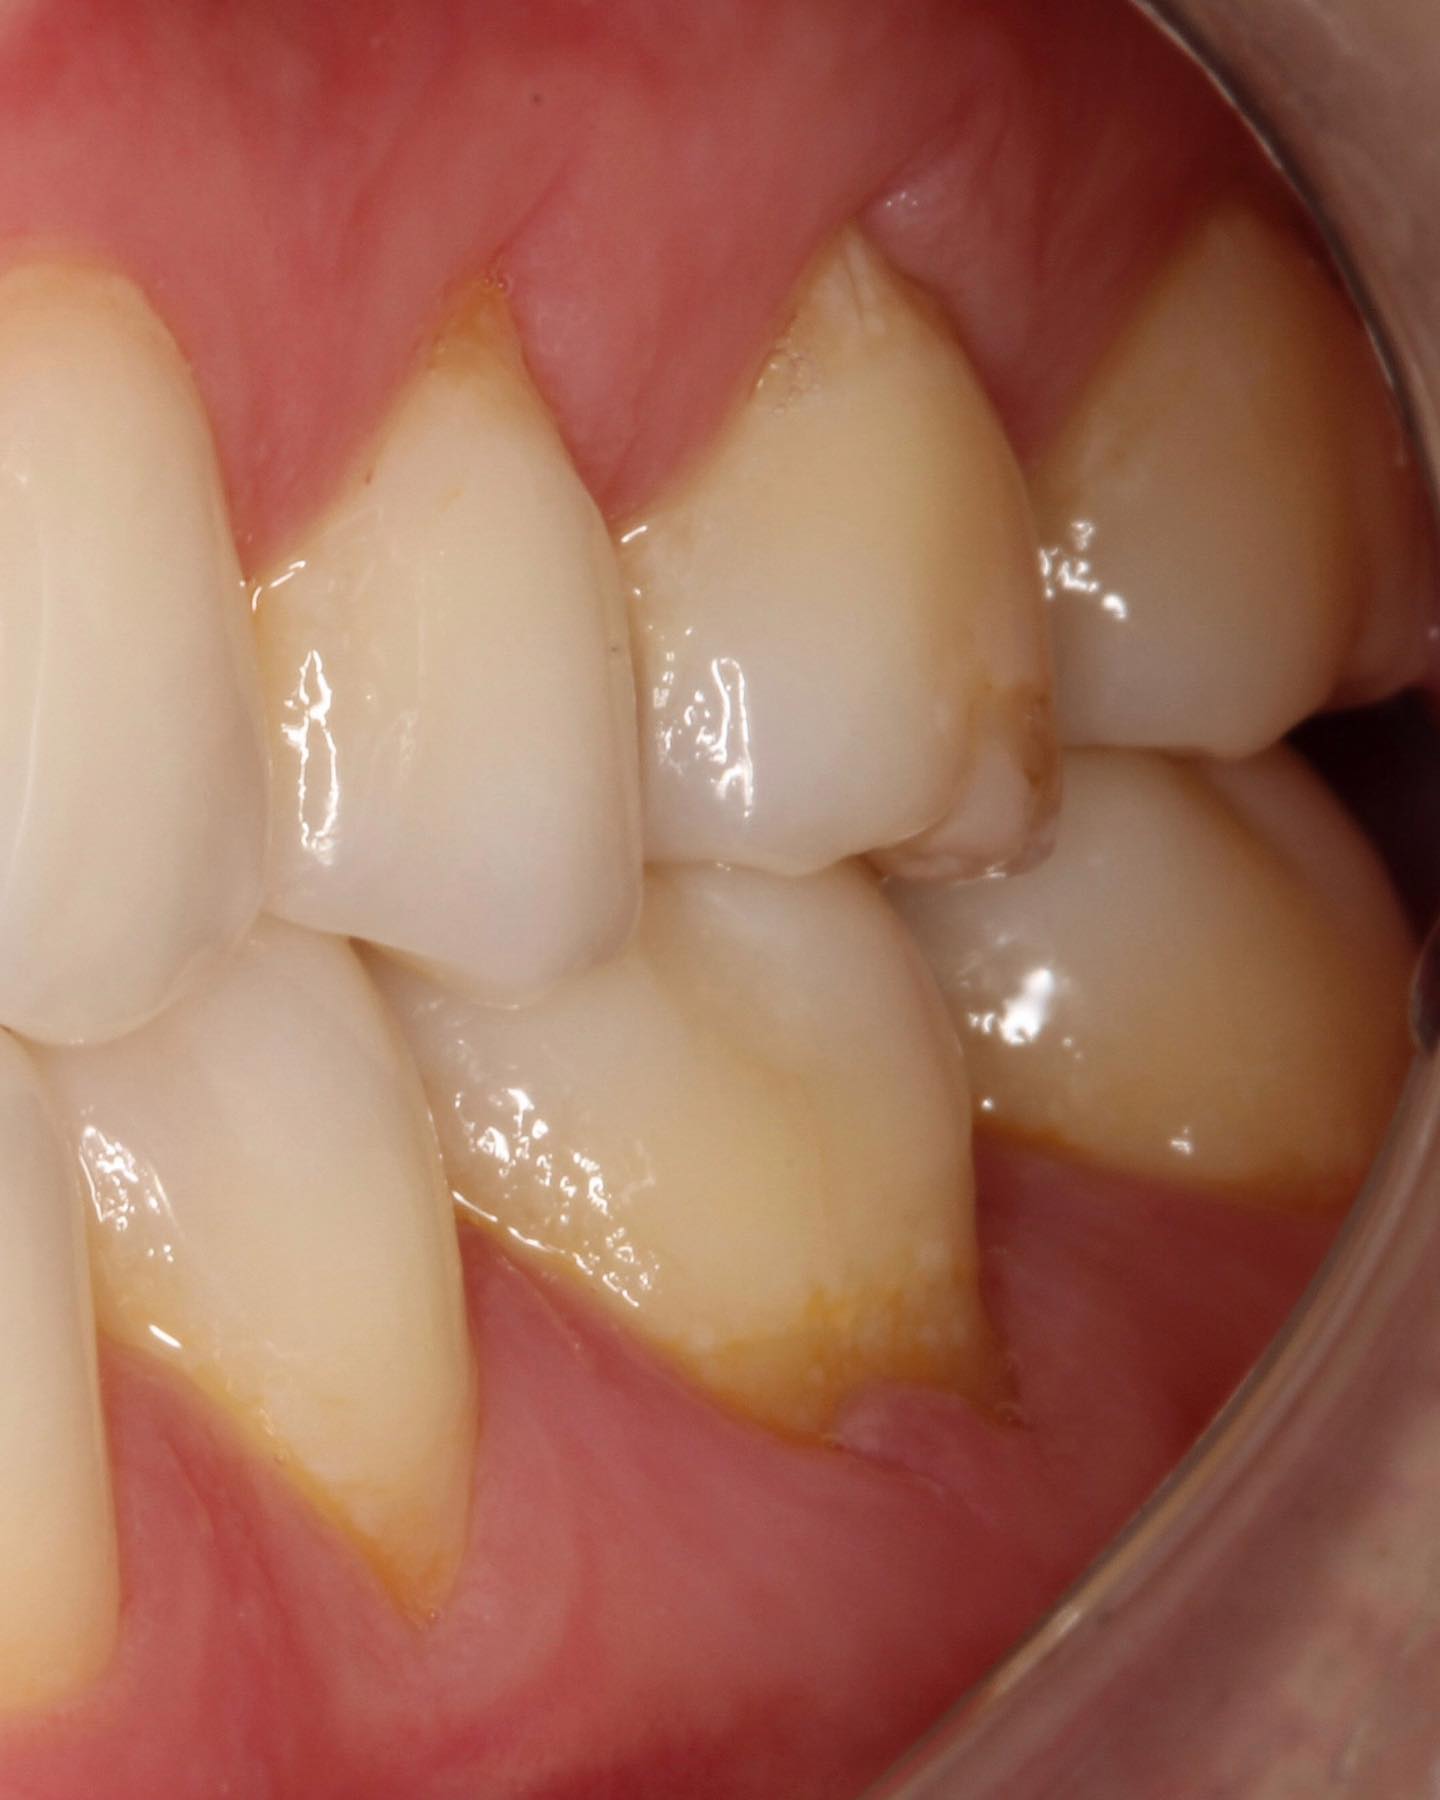

Guided Tissue Regeneration with Bone Graft & Growth Factors to Save teeth